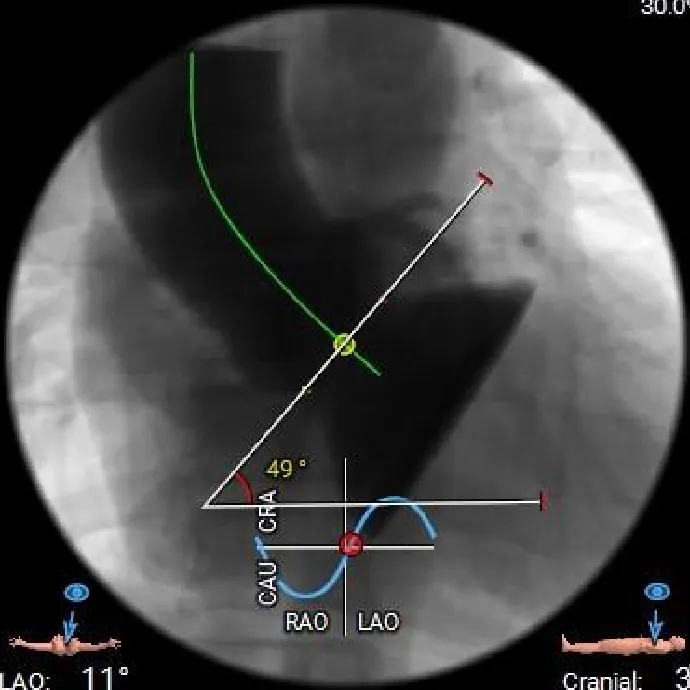

心脏角度

49°

57°

57°,近似横位心